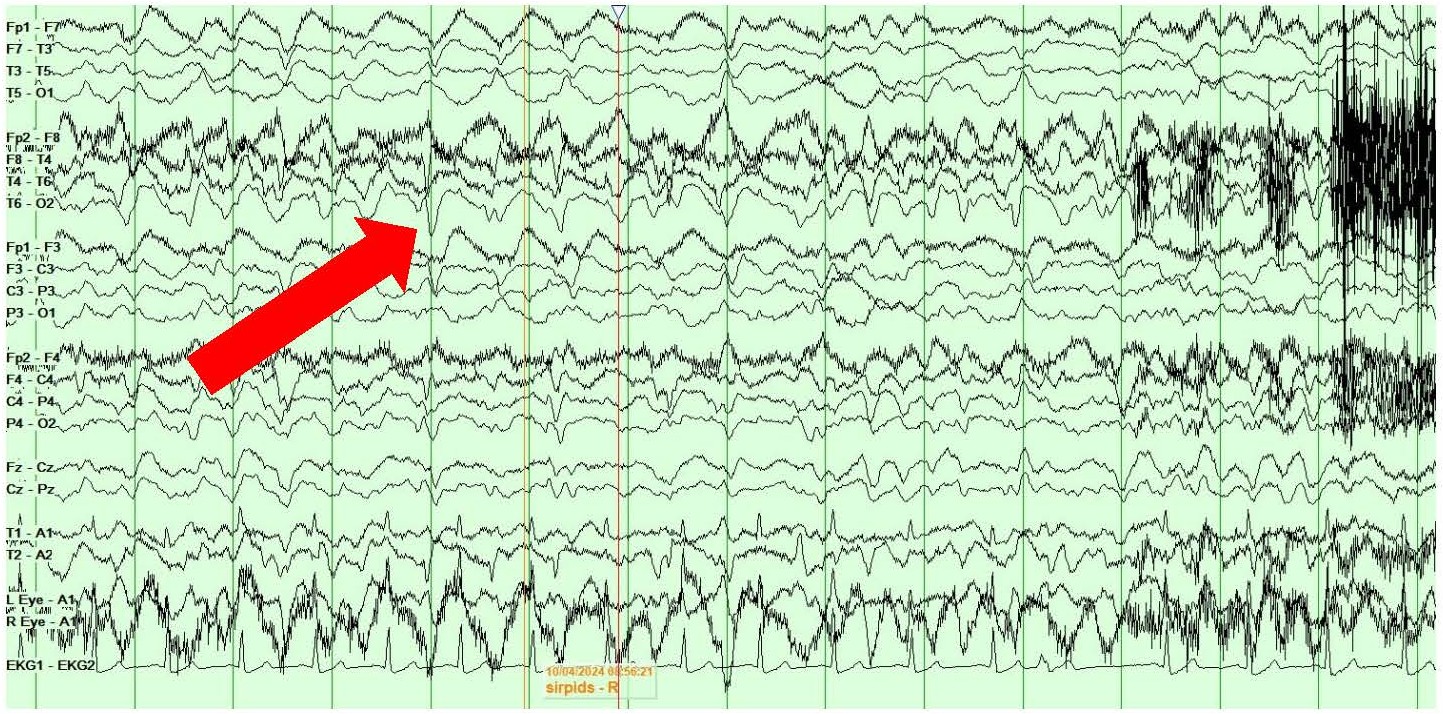

She also showed the presence of right hemispheric LPDs at 1-2 Hz and LRDA at 2-3 Hz that lasted for 1-10 minutes and occurred consistently with stimulation during physical manipulation or care by the medical providers and nursing staff (Figures 4A and 4B). These findings occurred independent of the previously described left hemispheric onset seizures mentioned above. They were felt to represent SIRPIDs (SI-LPDs and SI-LRDA).

Figures 4. A, B) Screenshots from Video EEG showing RIGHT hemispheric SIRPIDs provoked by stimulation (SI-LRDA and SI-LPDs) (marked by red arrows).